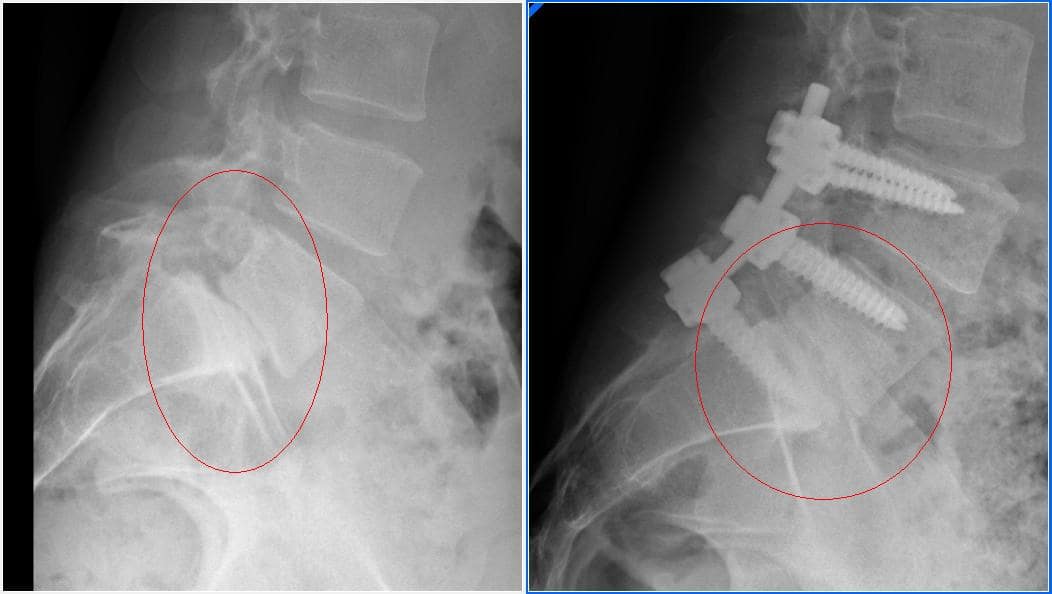

ESPONDILOLISTESIS.

La espondilolistesis es una alteración en la que una vértebra se desliza sobre otra. La espondilolistesis puede producirse porque hay un defecto en la vértebra consistente en la falta de unión entre la parte posterior de la vértebra y el cuerpo de la vértebra.

Otras causas de espondilolistesis pueden ser por traumatismos repetidos que provocan que se rompa el punto de unión entre la parte anterior y posterior de la vértebra, también puede producirse por causas congénitas o accidentes.